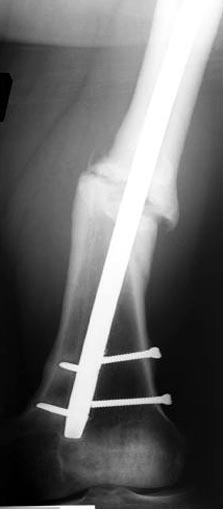

Снимки представлены: 1 мес; 3 мес; 1 год; 2 года, предоперационные и ротационная КТ грамма

Деформация:

Вальгус- 17 градусов

Рекурватум 5 градусов

Укорочение 2.5см

Ротационно 22 градусов внутренная

Смещение диафиза по поперечнику 75%